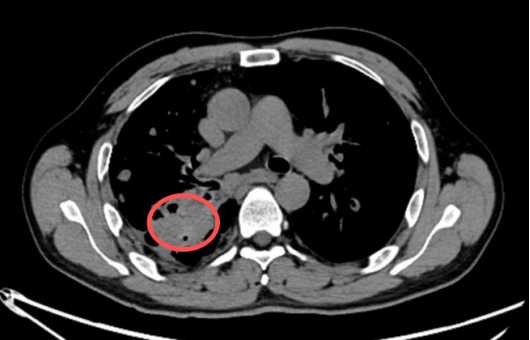

近日,在湘潭市第一人民医院放射科,上演了一场与死神的赛跑。一位年轻的肺结核患者突发咯血,命悬一线。幸运的是,医生凭借敏锐的洞察力,通过“支气管动脉CTA(即CT血管造影)”的检查,精准捕捉到了潜伏在其肺部深处的“隐形杀手”——Rasmussen动脉瘤。

Rasmussen动脉瘤,并非真正的肿瘤,而是一种“假性动脉瘤”,常发生于肺结核空洞患者,因结核病灶侵蚀肺空洞壁内的肺动脉分支血管壁,导致血管局部变薄、膨出,形成一个仅由纤维组织包裹的脆弱“气球”,极易破裂引发大出血,患者可能在短时间内因窒息或失血性休克而死亡。

为什么如此危险?Rasmussen动脉瘤伪装性强,在普通的胸部CT平扫中,这个动脉瘤可能仅仅表现为肺部的一个“结节”或“空洞内的软组织影”,极易被误诊为肺癌、炎症或普通的结核病灶;突发致命,它是导致肺结核患者大咯血的最主要原因,很多患者平时可能只有轻微的咳嗽或痰中带血,但一旦动脉瘤破裂,出血量往往巨大且迅猛;操作风险,若误诊为肿瘤并进行支气管镜活检或经皮肺穿刺,那无异于“引爆”炸弹,会导致瞬间的大出血,后果不堪设想。

在湘潭市第一人民医院的这例抢救中,支气管动脉CTA技术发挥了至关重要的作用。普通CT平扫,只能看到“山的轮廓”,可能只觉得那里有个包块。而支气管动脉CTA相当于给血管注入了“显影剂”,能清晰地看到“山里的水流”。它能明确显示病灶是否由血管组成,明确动脉瘤的位置、大小以及供血血管,为治疗提供精确“导航”,避免盲目操作带来的风险。